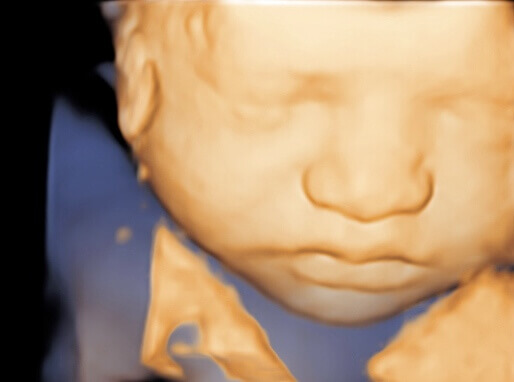

3D Ultrasound Image Gallery

3D Ultrasound Images